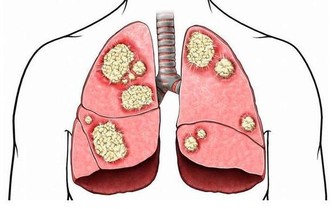

“腎虛”是很多人比較敏感的詞語,尤其是男性朋友。腎虛屬於一種中醫名詞,是指腎臟的精氣不足,主要症狀有四肢乏力、腰膝酸軟、盜汗、畏寒等等。腎虛不僅有損身體健康,同時也會降低生活品質。我們先來看一看百度百度怎麼解釋腎虛的:

腎虛指腎臟精氣陰陽不足。腎虛的種類有很多,其中最常見的是腎陰虛,腎陽虛。

腎虛的症狀:腎陽虛的症狀為腰酸、四肢發冷、畏寒,甚至還有水腫,為“寒”的症狀,性功能不好也會導致腎陽虛;

腎陰虛的症狀為“熱”,主要有腰酸、燥熱、盜汗、虛汗、頭暈、耳鳴等。現代科學證明,當人發生腎虛時,無論腎陰虛還是腎陽虛,都會導致人的免疫能力的降低,有更多的證據表明,腎虛發生時,腎臟的免疫能力降低,而腎臟的微循環系統亦會發生阻塞,腎絡呈現不通。所以對於腎虛的治療應防治結合。